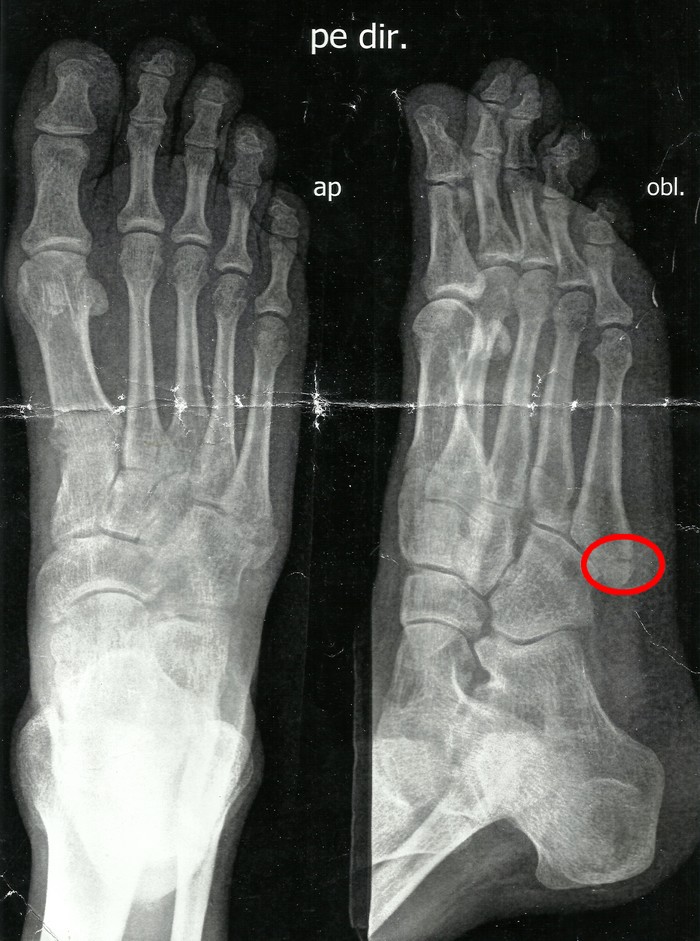

Fratura do 5º metatarso. Raio X tirado duas horas após a fratura, quando o pé fica acentuadamente inchado e a dor é bruta

Fratura do 5º metatarso. O mesmo Raio X anterior, porém,tirado num outro ângulo

Fratura do 5º metatarso. Raio X tirado 15 dias após a fratura, em que se observa uma sensível melhora na calcificação do osso

Fratura do 5º metatarso. Raio X tirado 40 dias após a fratura, com o osso praticamente consolidado.